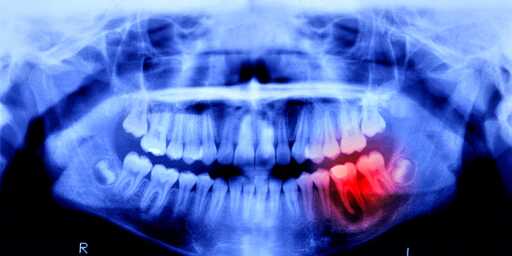

There are larger, more established correlational studies that show a link between dental health and overall physical health as well. There needs to be much more study done but preliminary evidence would suggest that preventive dental care provides for a cheaper overall health cost for a person over their lifetime.